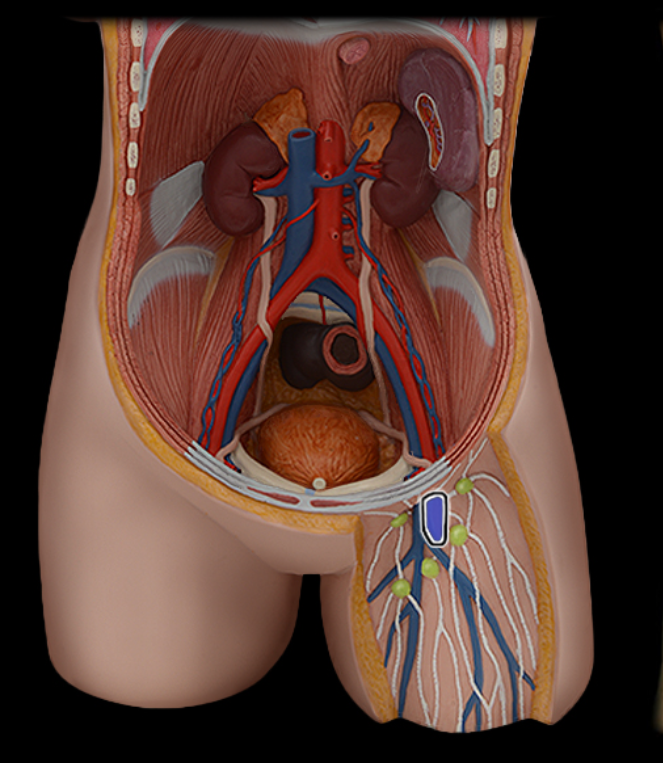

Abdominal aorta

Common iliac a.

Common iliac v.

External iliac a.

External iliac v.

Femoral a.

Femoral v.

Gonadal a.

Gonadal v.

Inferior vena cava

Lumbar a.

Lumbar v.

Renal a.

Renal v.

Superior mesenteric a.